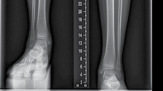

| Preoperative planning See ‘Principles of limb reconstruction’ (p. 427) (Figure 15.8). Surgical technique Corticotomy Landmarks | |||

| Figure 15.8 Tibial Ilizarov frame for lengthening. | |||

| Figure 15.9 Radiograph of tibial Ilizarov frame for lengthening. | |||